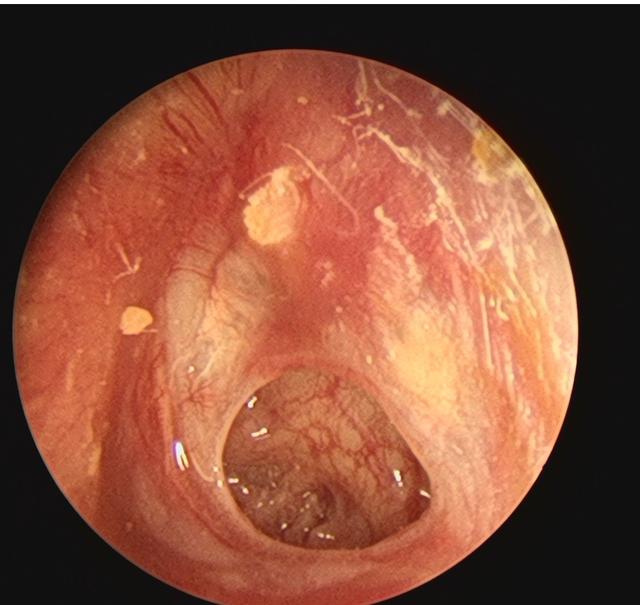

分泌性中耳炎内镜检查显示鼓膜内陷橙红油亮.png

图片尺寸735x592